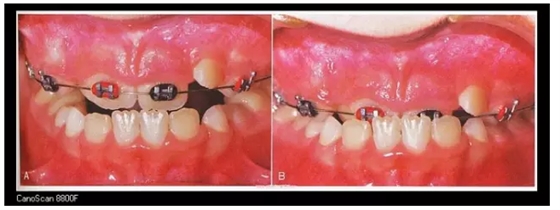

左邊為金屬托槽,右側(cè)上頜Damon Clear透明自鎖托槽,下頜Damon Q金屬自鎖托槽。